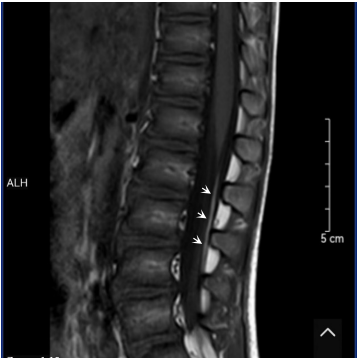

为查清原因,家人带着小健先后前往多家医院,尝试过吃西药,也尝试用中药改善,但效果都不佳,后来前往广州某医院做了详细的B超、磁共振等检查,发现:(1)骶1及以下水平椎板未闭;(2)俯卧位脊髓移动不显著,存在终丝脂肪浸润可能。

胡震主任详细了解了小健的病情并仔细查看了相关检查,向小健的父母解释:“终丝脂肪浸润导致终丝高张力是一类隐匿性脊髓栓系,由于患者脊髓圆锥在正常位置,临床症状常常以遗尿、便秘、腰痛等不典型症状为主。根据小健的症状和外院的检查结果,基本上可以判断是终丝脂肪浸润,但是由于外院的核磁共振检查没有包含特定的脂肪序列,所以还需要补充一个特殊的脂肪序列检查来确诊。”于是,胡震联系了佛山妇幼放射科,通过3.0T核磁共振对小健进行了详细的检查,最终确诊为终丝脂肪浸润,胡震建议进行手术治疗。